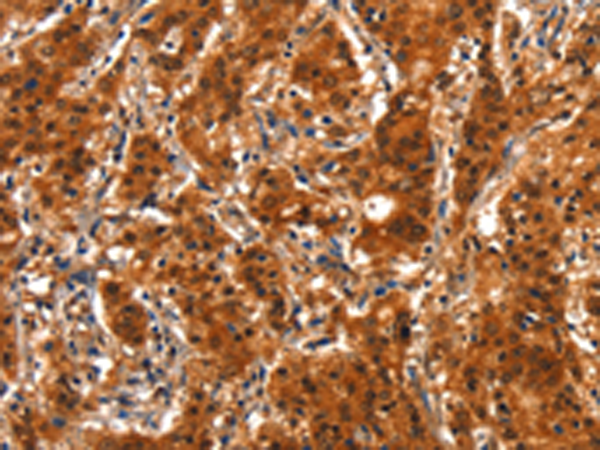

分类: 科研抗体货号: P11195别名: APO-CIV; APOC-IV应用: IHC反应种属: Human